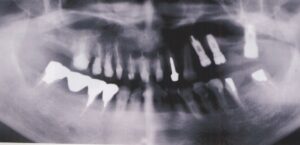

- 10年前から他の歯科医院にて部分的な治療を受けたが、見た目が良くない・噛めないとのことで再治療を希望された。アングルクラスⅠであった。左上奥歯がない。

- 上顎左側にインプラントを3本し、

- オールセラミック4本にて被せ物を行なった。

- 審美的な仕上がりで、患者自身も満足した。23年経過し良好である。

現在は2〜3ヶ月おきのメインテナンス中である。